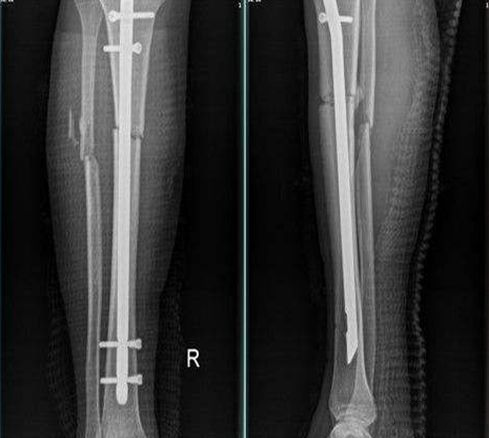

髓内针内固定

无论闭合性或开放性小腿骨折均适用,尤其是后者,更具有适用价值。

闭合复位仍不能达到满意复位;有较严重软组织损伤的胫腓骨干骨折,或合并小腿筋膜间隔综合征,或肿胀严重起水泡。